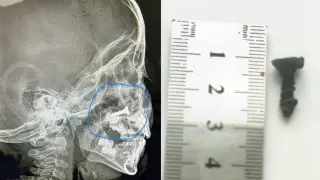

"Снимок показал наличие шурупа в носу малыша. Размер его - два сантиметра. Он находился там около полугода, но шуруп никак не беспокоил мальчика, поэтому родители не обращались за медицинской помощью. А на днях его мама решила провести рентген-обследование своему ребенку. Там-то все и обнаружилось. Сразу же малыш был госпитализирован в отделение, ему проведена операция под общим наркозом. Инородное тело успешно извлечено. Операцию провел молодой лор-врач Айбол Конысбаев. Ребенок чувствует себя хорошо", - сказал он.

Фото предоставлено врачами многопрофильной детской больницы Кызылорды